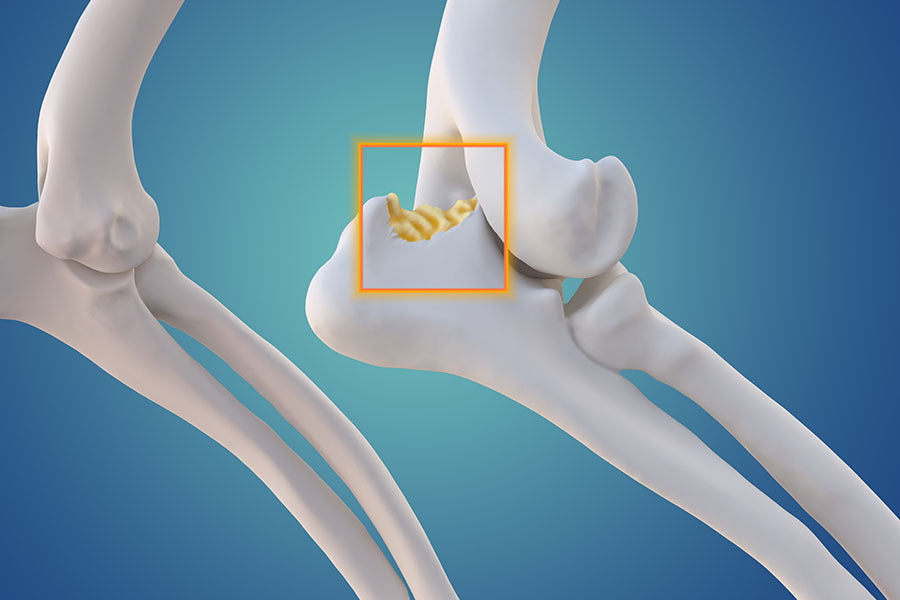

Osteoarthritis, also known as degenerative joint disease, is one of the most common joint disorders in dogs. It occurs when the cartilage that cushions the joints deteriorates, leading to pain, inflammation, and reduced mobility. Osteoarthritis is particularly prevalent in older dogs but can also affect younger dogs due to injury or genetic predisposition.

Similar to hip dysplasia, elbow dysplasia is a genetic condition that affects the elbow joints. It’s particularly common in breeds like Rottweilers, Labrador Retrievers, and Bernese Mountain Dogs. Elbow dysplasia can cause lameness and discomfort, and if left untreated, it can result in chronic pain and arthritis.